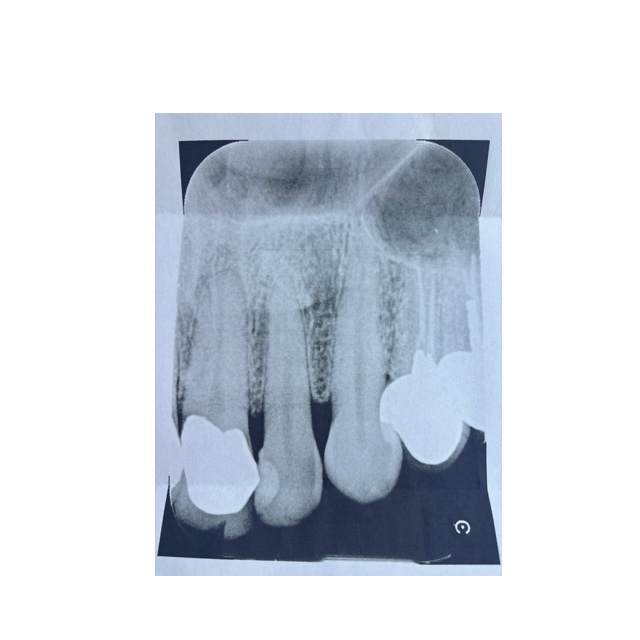

[写真あり] 左上下6・7番抜歯、左上2番の前歯の動揺が気になる

>歯周病、骨など問題はないと思います?

>先生から見て、この歯の寿命は長いと思いますか?

レントゲンを見てそれをコメントするのは、「診断」になるので私はお断ります。

他の先生からの意見を待ってみてください。